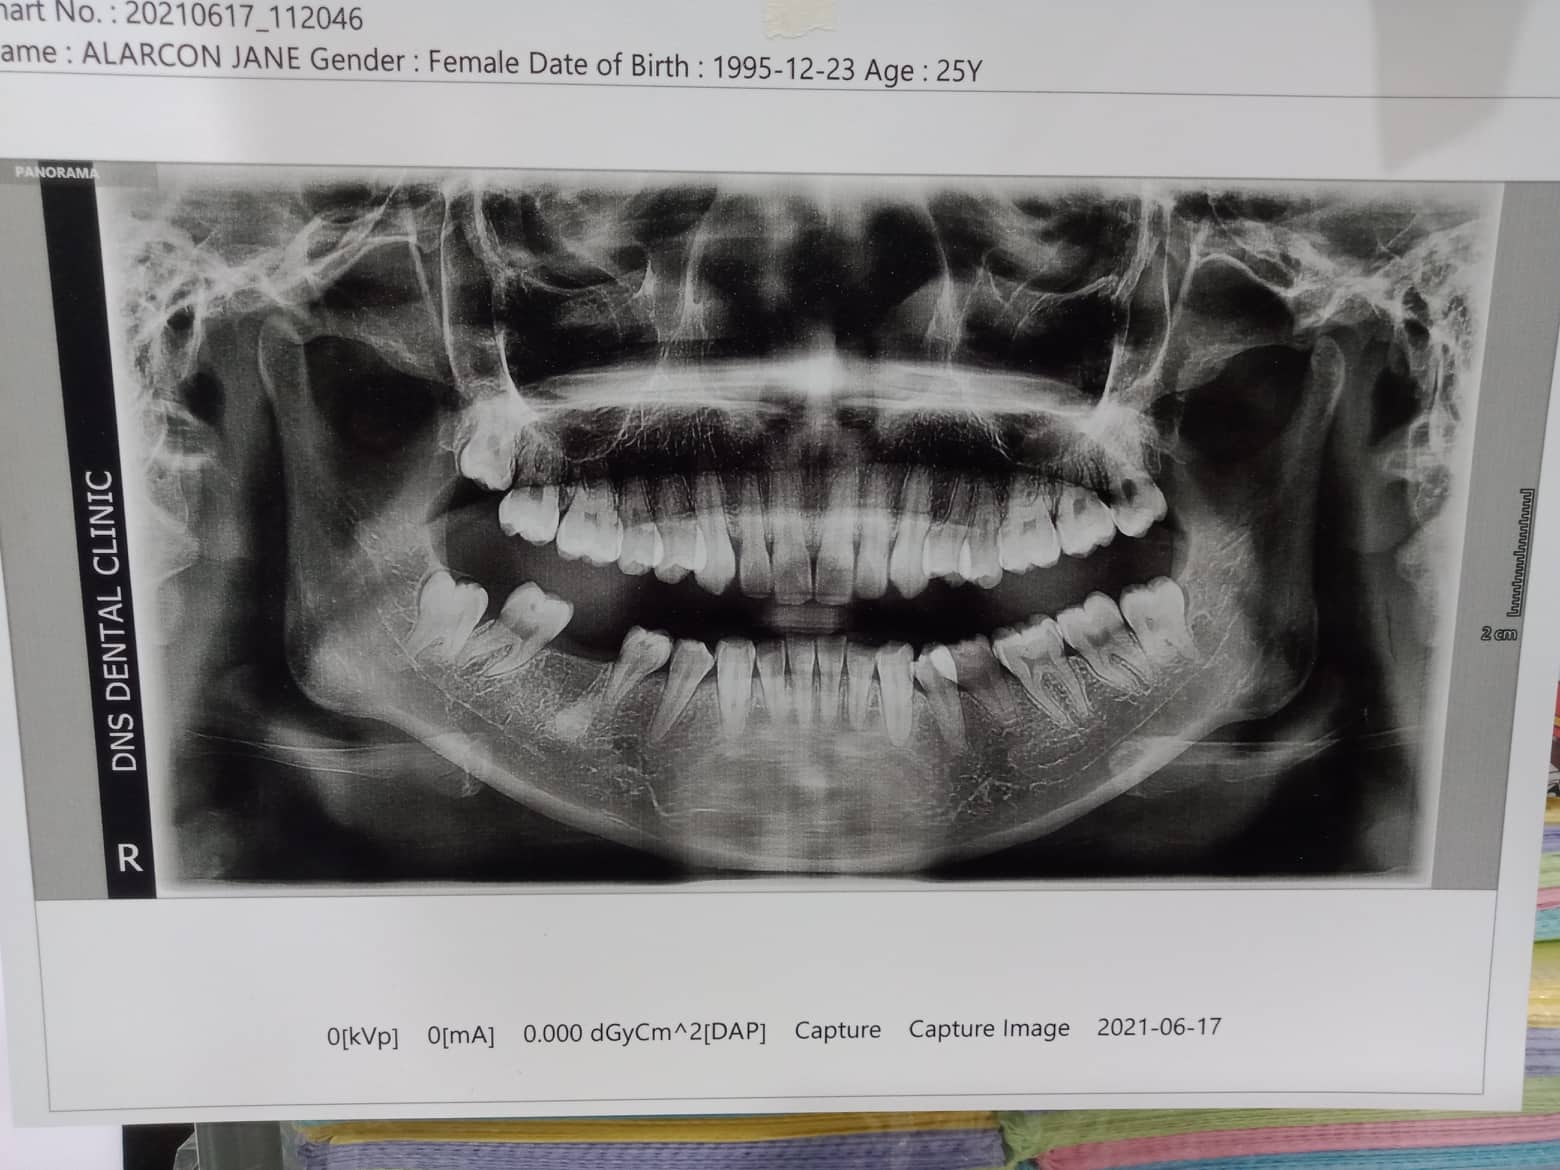

Edit Record Check our patient data records. Add patient information Patient Info Profile picture Last Name First Name Middle Name Birthdate Age Street Barangay City Country Zip Code Contact number Email Procedure 07/27/21- U16niti/ L14niti RW 11/21 09/08/21 - 16niti U/16nitiL 10/8/21- 16ss U/L upper to left/ move 34 towards mesial 11/12/21- 16ssUL/ #35 installed- to upright double wire 14niti 1/7/22- same wire/ S- elastic L button 35 to 24-25- fox 02/25/22- close space on 13-12 ***for reshape 35 one side right elastic loop to 45 04/02/22- reshape 35 with fiber same wire. RPI 13 and 23. distalize 05/06/22- 16 ss U/ 18 niti L/ class 2 elastic rabbit 06/18/22- same wire/ class 2 right chimunk/ left rabbit 08/06/22 - same wire/ Class 2 elastic chimunk 09/24/22- 16ss L/ same wire upper. class 2 rabbit 11/18/22- adj 01/07/23- ADJ 04/1/23- 16x16 ss UL chain Upper/ intrude #21 05/26/23- U: 16ss wire, 22-12 individual, chain 26-16 L: same wire; individual / Rabbit elastics 06/30/23- 16x22 UL Upper chain 26 occlusal deepseated caries with CAOH 08/17/23 -same wire chain upper individual lower for removal oct-nov 09/29/23- UL legature wire.. **** For removal for October *** 01/13/24 brace removal 08/03/24 Exo #38 gel foam suture ozone 04/09/25 OP File 302095548_384062630396548_1908952325740404096_n.jpg File 2 302234576_799187434601578_178624593392175074_n.jpg File 3 File 4 File 5 File 6 File 7 File 8 File 9 File 10 File 11 File 12 File 13 File 14 File 15 File 16 File 17 File 18 File 19 File 20 Retain Record Retain Record Yes No Save Your Changes